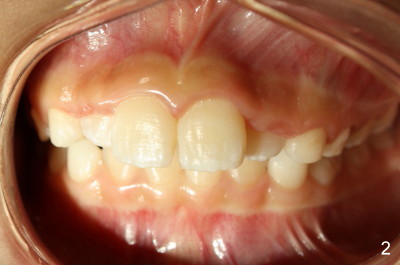

Eight-year-four-month-old boy shows early signs of Class II Division I malocclusion (Fig.2-5).  Panoramic X-ray was taken when he was 5 years 10 months old (Fig.1).

Is there any indication for phase I ortho (interceptive treatment)?  In my opinion, early orthodontics will improve appearance.  Additional Class II retraction may change canine and molar Class II occlusion into Class I so that the mandible may develop normally before permanent dentition.  If the early treatment is not done until permanent dentition as parents hope, it is most likely that orthodontics will be conducted with extraction at least two upper bicuspids.  The father has typical Class II Division I malocclusion.  What do you think?  Thanks.

2nd reply Also Xin in your case of the 8 y.o. boy, I could make the argument that the lingually positioned #7 and #10 may ultimately restrict the lower jaw from growing normally anteriorly.  Their position may very well indeed be in the way.  Check out occlusion from your pictures.  I can explain better in person perhaps.